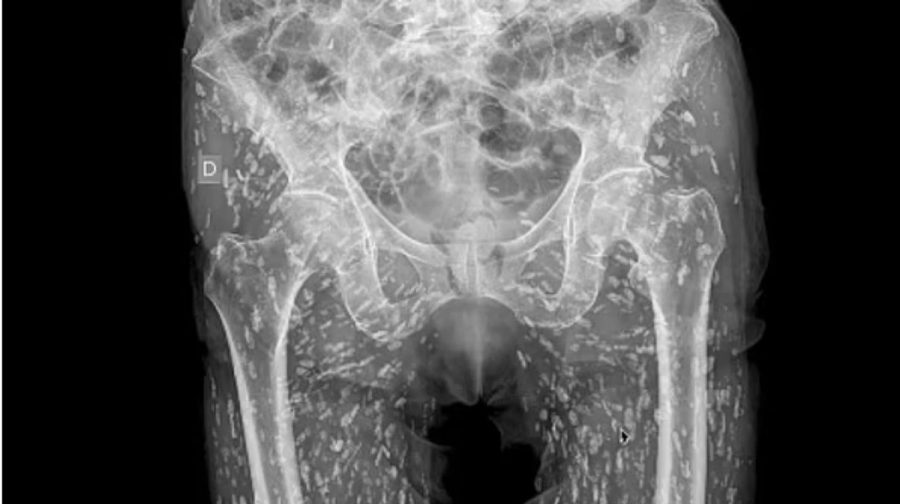

ഫ്‌ളോറിഡയിലെ എമർജൻസി ഡോക്ടറായ സാം ഗാലിയുടെ എക്സ് പോസ്റ്റ് സമൂഹമാധ്യമങ്ങളിൽ ചർച്ചയാകുന്നു.  കടുത്ത ഇടുപ്പ് വേദനയുമായെത്തിയ ഒരു യുവാവിന്റെ എക്സ്റേയിൽ കണ്ട ഞെട്ടിക്കുന്ന ദൃശ്യങ്ങൾ പങ്കുവെച്ചുകൊണ്ടായിരുന്നു ഈ പോസ്റ്റ്.

ഇന്നുവരെ കണ്ടതില്‍ ഏറ്റവും 'ഭയാനകമായ എക്‌സറേ ദൃശ്യങ്ങള്‍' എന്നാണ് ഡോ. സാം എക്സിൽ കുറിച്ചത്. ശരിക്ക് പാകം ചെയ്യാതെ പന്നിയിറച്ചി കഴിച്ചതിലൂടെ യുവാവിന്റെ ശരീരത്തിനുള്ളിലെത്തിപ്പെട്ട നാടവിര മുട്ടയിട്ട് പെരുകിയ ദൃശ്യങ്ങളായിരുന്നു എക്സ്റേയിൽ ഉണ്ടായിരുന്നത്.

ഏത് സാഹചര്യത്തിലായാലും ശരിയായി വേവിക്കാതെ പന്നിയിറച്ചി കഴിക്കുന്നത് അപകടകരമാണെന്ന മുന്നറിയിപ്പ് കൂടിയാണ് ഡോ. സാം ഈ പോസ്റ്റിലൂടെ നൽകുന്നത്. വേദന സഹിക്കാൻ വയ്യാതെ ആശുപത്രിയിലെത്തിയ യുവാവിന്റെ ശരീരത്തിനുള്ളിൽ ഇടുപ്പിലും കൈകാലുകളിലുമായി നാടവിരകളുടെ നൂറുകണക്കിന് മുട്ടകളാണ് കണ്ടെത്തിയത്.

'നാടവിരകളുടെ മുട്ടകൾ യുവാവിന്റെ ശരീരത്തിനുള്ളിൽ ഏകദേശം എല്ലായിടത്തുമുണ്ടായിരുന്നു. അവ എണ്ണാനാവാത്ത വിധം പെരുകിപ്പോയിരുന്നു.  ശരീരത്തില്‍ എവിടേക്ക് വേണമെങ്കിലും ഇവയ്ക്ക് സഞ്ചരിക്കാനാവും. ഈ യുവാവിന്റെ  ഇടുപ്പുകളുടെയും കാലിന്റെയും  ഭാഗത്താണ് അവ  കൂടുതലായി അടിഞ്ഞുകൂടിയിരിക്കുന്നത്. - സാം  കുറിച്ചു.

ഈ അവസ്ഥയെ ടെനിയ സോലിയം ഇന്‍ഫെക്ഷന്‍ എന്നാണ് അറിയപ്പെടുന്നത്. ഈ അപകടകരമായ അണുബാധ നാഡീവ്യൂഹത്തെയോ തലച്ചോറിനെയോ  ബാധിച്ചാല്‍ രോഗിയുടെ നില അപകടാവസ്ഥയിലാവും.യുവാവിനെ പ്രാഥമികമായി പരിശോധന നടത്തിയപ്പോൾ എന്താണ് ഇടുപ്പ് വേദനയുടെ കാരണമെന്ന് കണ്ടെത്താന്‍ ഡോക്ടർ‌ക്ക് കഴിഞ്ഞിരുന്നില്ല. അങ്ങനെയാണ് എക്‌സ്‌റേ വഴി കാരണം കണ്ടെത്തിയത്.

X-ray revealed creatures were breeding inside man's body after common kitchen mistake. A man was left in horror after an X-ray revealed his body was riddled with tapeworm eggs.The image shows hundreds of 'rice grain' nodules that turned out to be cysts caused by the parasitic infection.Dr Sam Ghali, an urgent care doctor in Florida, shared the photo on social media describing it as one of the 'most insane X-rays' he'd ever seen.